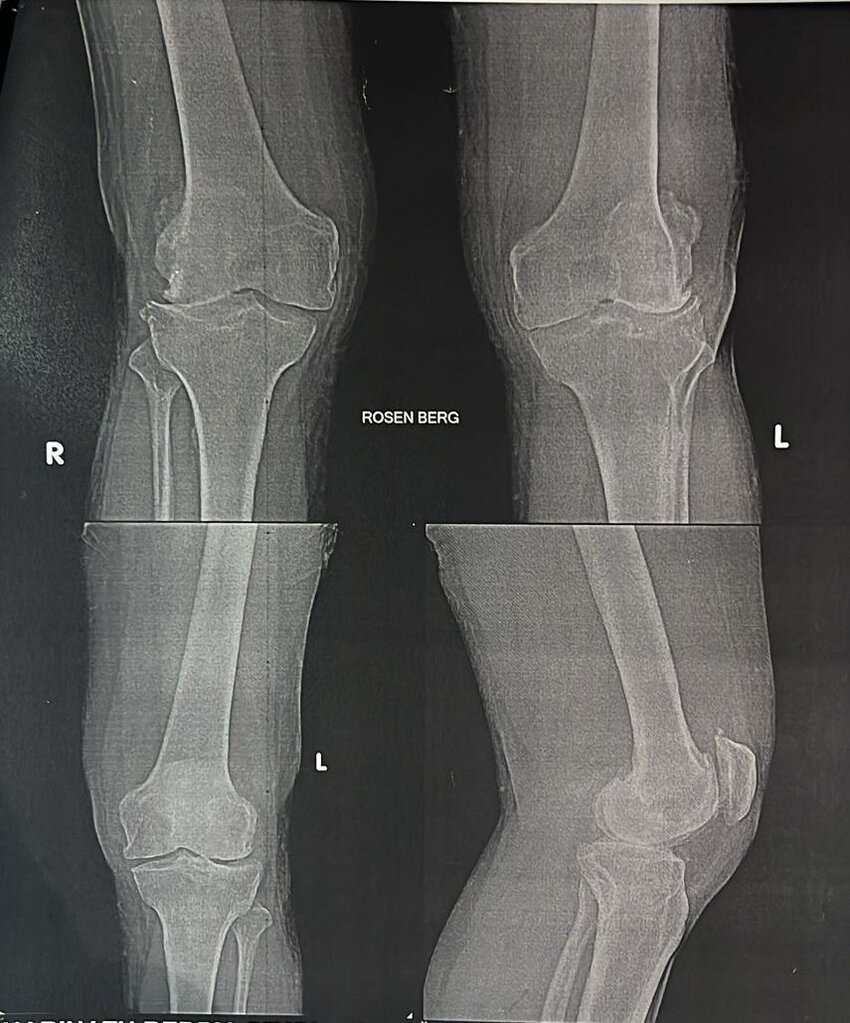

1. Osteoartritis : Merupakan bentuk rematik yang paling umum, disebabkan oleh kerusakan kartilago yang melapisi ujung tulang, sehingga tulang bergesekan langsung satu sama lain.

Penyakit rematik, terutama osteoartritis dan rheumatoid arthritis, merupakan masalah kesehatan yang umum di Indonesia. Berdasarkan data Riskesdas 2018, prevalensi penyakit sendi di Indonesia pada populasi dewasa di atas 18 tahun adalah sekitar 7,3%. Osteoartritis merupakan bentuk rematik yang paling sering ditemui di Indonesia, terutama pada kelompok usia lanjut. Faktor risiko utama yang mempengaruhi tingginya angka kejadian rematik di Indonesia termasuk penuaan populasi, obesitas, dan cedera sendi. Selain itu, faktor genetik dan lingkungan juga turut berperan dalam peningkatan angka kasus rematik.

1. Osteoartritis: Penyebab utama adalah keausan kartilago sendi seiring bertambahnya usia. Faktor risiko meliputi usia lanjut, obesitas, dan cedera sendi.

1. Osteoartritis : Nyeri sendi, terutama setelah aktivitas fisik, kekakuan pada pagi hari, dan berkurangnya fleksibilitas sendi.